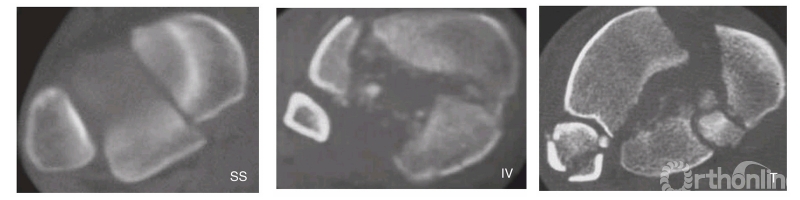

Topliss等分析了126例Pilon骨折患者中的108张CT片,提出了累及关节的6个主要骨块为前侧、后侧、内侧、前外侧(Tillaux-Chaput)、后外侧(Volkmann)和冲床样(Die-punch)骨折块。同时,他们根据主要骨折线的方向把骨折分为两大类(6%无法辨认,5%为边缘性骨折)。主要骨折线前后方向位于矢状面占33%(图18-2-6),可分为纵向分裂型(SS)、倒V型(IV)和T型(T),纵向分裂型为相对较低能量下出现的单一骨折线,后两者为能量继续增加造成的结果;主要骨折线内外方向位于冠状面占56%(图18-2-7),可分分为横向分裂型(CS)、前侧分裂型(AS)、后侧分裂型(PS,后Pilon骨折)、V型(V)和Y型(Y),后两者也是相对较高能量损伤的结果。他们认为,矢状面骨折通常存在内翻成角,常发生于高能量损伤的年轻患者;冠状面骨折倾向于存在外翻成角,常发生于低能量损伤的老年患者。

Pilon骨折主要骨折线位于矢状面CT表现

SS:纵向分裂型;IV:倒V型;T:T型